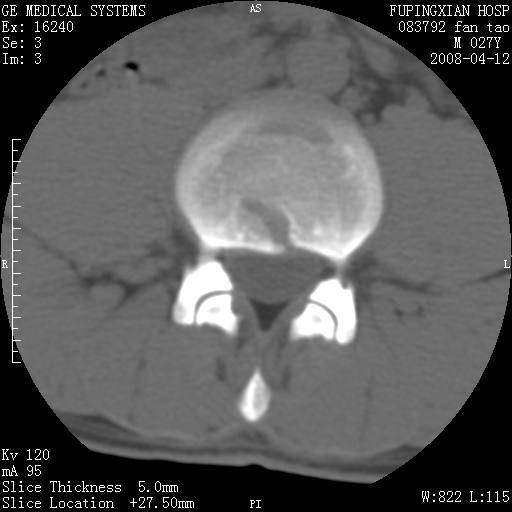

以下是引用前行在2008-4-13 13:53:00的发言:[br]椎间盘髓核终板下突出形成许莫氏结节及椎间盘突出,建议mr检查

以下是引用xclzq_910在2008-4-13 12:43:00的发言:[br]这个应该没什么了,椎间盘突出后反应性骨质吸收硬化.建议mr